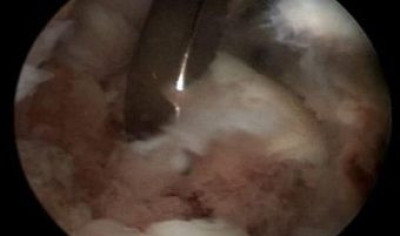

Se está extrayendo un fragmento óseo dentro del codo